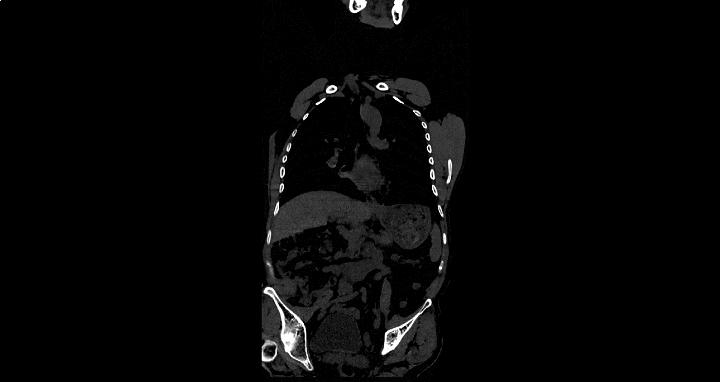

近日,经多方打听,她在丈夫的陪同下来到郑州市管城中医院骨伤科求医。郑州市管城中医院副院、骨伤科首席专家王长勇接待了刘女士,那天,年轻貌美却显憔悴的她,弯腰驼背、一瘸一拐地来到诊室。王院长检查她的 脊柱已处于僵直状态,无法平躺 ,完全不能直立靠墙, “4字试验”明显阳性,这时王院长心中已经有谱, 当即为她做腰椎MRI、骶髂关节MRI、炎症指标等相关检查。果然,不出所料,折磨她这么久的病根水落石出——强直性脊柱炎(“强直”)。

多数患者随着病情的进展,由腰椎向胸、颈部脊椎发展,出现相应部位的疼痛、活动受限,甚至是脊柱畸形(呈“竹节样”改变)。少数病人可出现低热、疲劳、体重下降、贫血等情况。如果眼部受累患者还可以出现畏光、流泪、眼睛疼痛等表现。